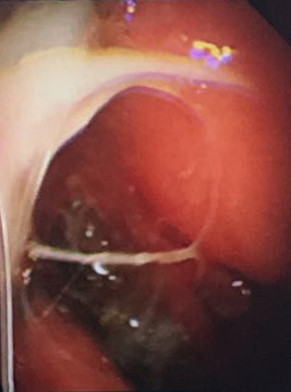

多發(fā)黃白色小結節(jié)

7月21日建立人工氣胸,擴張肺部。7月22日,由周傳毅主任、張健主治醫(yī)師共同實施了胸腔鏡檢查,并活檢取出多處胸膜小結節(jié)。術后經病理診斷,確診為結核性胸膜炎。檢查過程無任何不適,后續(xù)配合抗結核藥物治療,王爺爺恢復良好,已出院返家。

我院呼吸內科采用改良型“軟式胸腔鏡”,該新設備軟硬結合,前端可彎曲,能多方向觀察胸腔內改變,比老式“硬式胸腔鏡”的探查視野更大,診斷更準確。